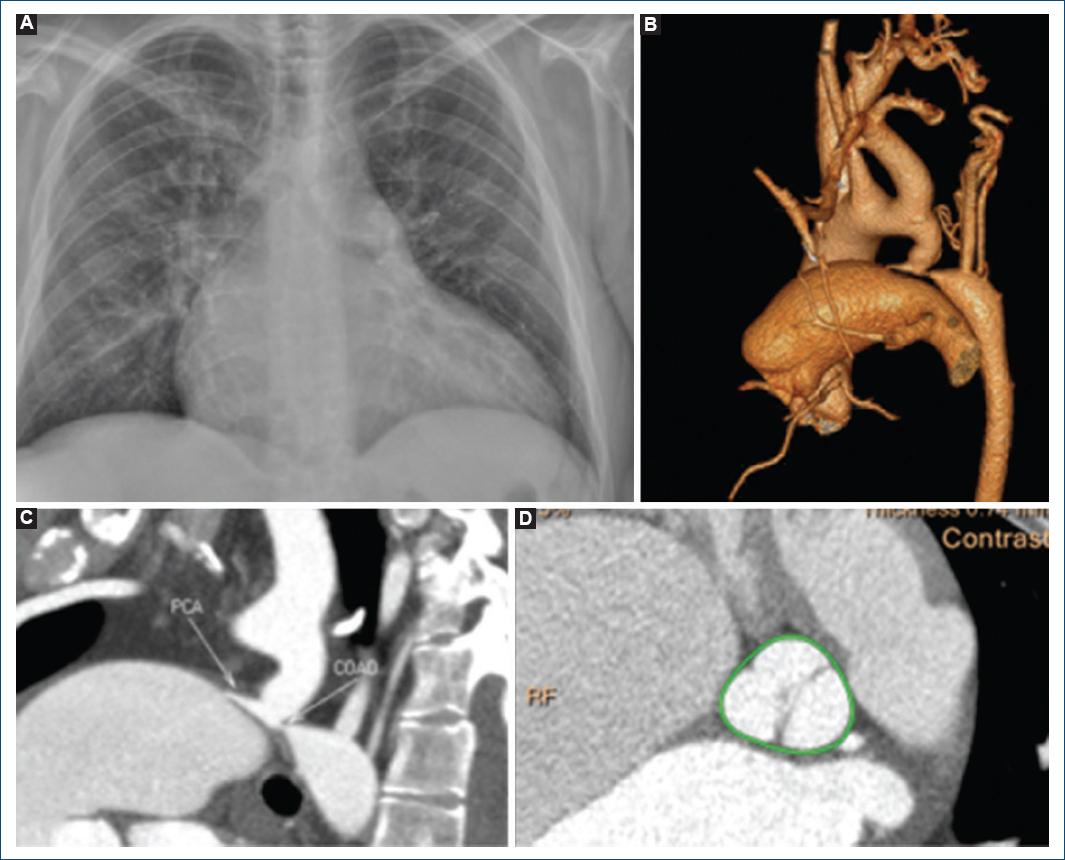

Los estudios bioquímicos estuvieron en parámetros normales. La radiografía de tórax (Fig. 1A) mostró cardiomegalia de grado III y el electrocardiograma mostró ritmo sinusal con onda p pulmonar.

Figura 1 A: radiografía de tórax con cardiomegalia y cefalización de flujo. B: tomografía cardiaca con reconstrucción 3D demostrando coartación posductal con persistencia del conducto arterioso. C: tomografía contrastada, delimitando la coartación y la persistencia del conducto. D: aorta bivalva.

El ecocardiograma mostró aorta bivalva tipo L-R con estenosis moderada, ventrículo izquierdo dilatado con fracción de eyección del 25%, strain longitudinal de −2.4% y disfunción sistólica del ventrículo derecho. En el ecocardiograma transesofágico se observó persistencia del conducto arterioso con flujo de izquierda a derecha.

La tomografía cardiaca (Figs. 1B y C) documentó aorta bivalva (Fig. 1D), coartación posductal de 4.1 × 3.6 mm en su segmento más estrecho a 30 mm de la subclavia izquierda, así como persistencia del conducto arterioso con boca pulmonar de 2 mm y foramen oval permeable.